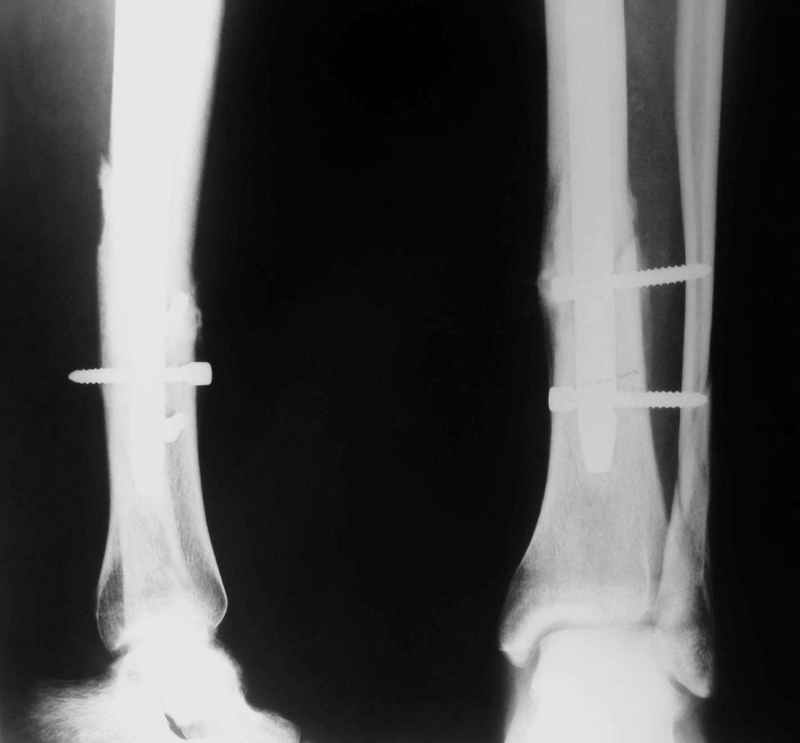

Re: Потекли блокирующие винты, после интрамедулярн

Рентгенограмы